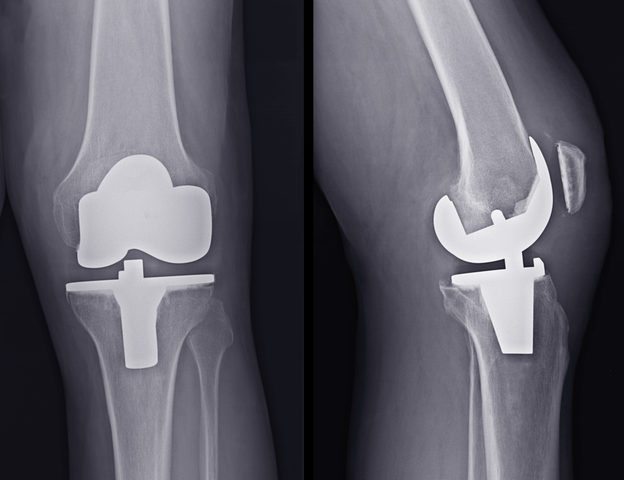

During knee replacement surgery, knee joints damaged by arthritis can be replaced with an artificial knee, also known as a prosthetic knee. A prosthetic knee can help restore mobility and reduce pain in the affected knee. When the joints of both knees are damaged, double knee replacement may be recommended. A doctor will usually recommend…

Knee replacement removes a damaged knee joint and replaces it with an artificial joint. Your knee is the largest joint in your body. It’s involved in most of your movements throughout the day. The goal of knee replacement, also known as knee arthroplasty, is to restore pain-free range of motion and function. When it comes…